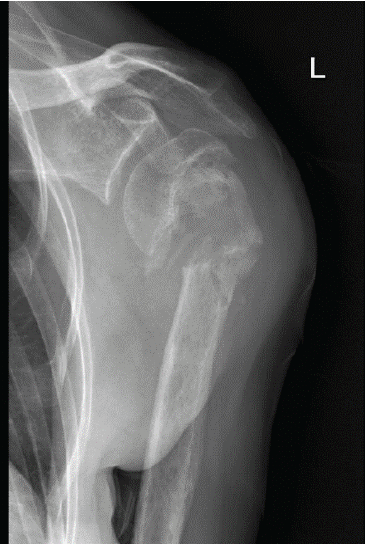

The patient reported left shoulder pain caused by nonunion of a proximal humerus fracture that was sustained in a fall 5 months earlier and managed with non-operative treatment (Fig. 1).

Figure 1: Pre-operative anteroposterior radiograph of the left shoulder of a 67-year-old woman with osteogenesis imperfecta showing atrophic nonunion of a proximal humerus fracture.